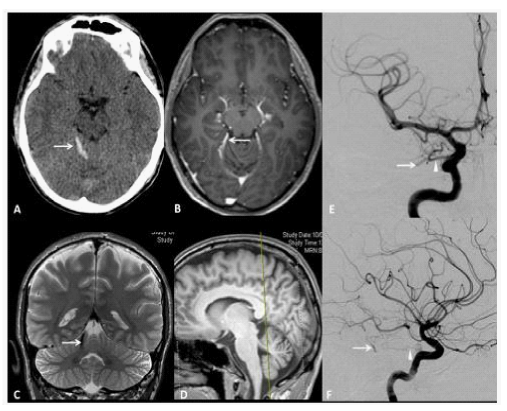

Figure 5 A 33year old man presenting with sudden headache and meningiomes. A. Axial Head CT scan shows a pialhemorrhage (white Arrow) on the surface of the right anteriorquadrangular lobe of the cerebellum. B. Axial T1-weighted enhanced MRI showing a small flow void in contact with the right posterior 1/3 of the free tentorialedge, corresponding to a suspended veinbridgingbetween the tentorialconvexity of the cerebellum to a tentorialvenouslacuna. C. Coronal T2-weighted High resolution image, showing the bridgingvein (white Arrow). D. Sagittal T1-weighted reference image. The yellow trait corresponds to the level of the coronal cutdepicted in the C box. AP and F, LL views of DSA, showing a grade III Borden without venous ectasia, Grade III Cognard IDAVF supplied by the right tentorialartery (Bernasconi and Cassinariartery, white arrowhead), branch of the meningohypophisealtrunk, originatingfrom the intracavernous ICA and drained by the small suspended vein (white arrow) tributary of a tentorialvenouslacunaseen on MRI, whichis the source of hemorrhage.

Figure 6 A 50year old man presenting with left partial rolandic seizures. A, T2, B, T2*, C, T1-weighted MR sequences before and D, after gadolinium injection, axial view, showing flow voids (white arrows) without haemorrhage in the right rolandic area.

Figure 7 A, B, right and C left external carotid artery injections DSA confirms a Borden grade III IDAVF with venous ectasias (asterisk), which corresponds to Cognard grade IV, with bilateral arterial supply from the middle meningeal and superficial temporal arteries and direct CVD through dilated pial veins tributary of the superior sagittal sinus. D, Lateral projection DSA does not show ICA supply to the fistula.